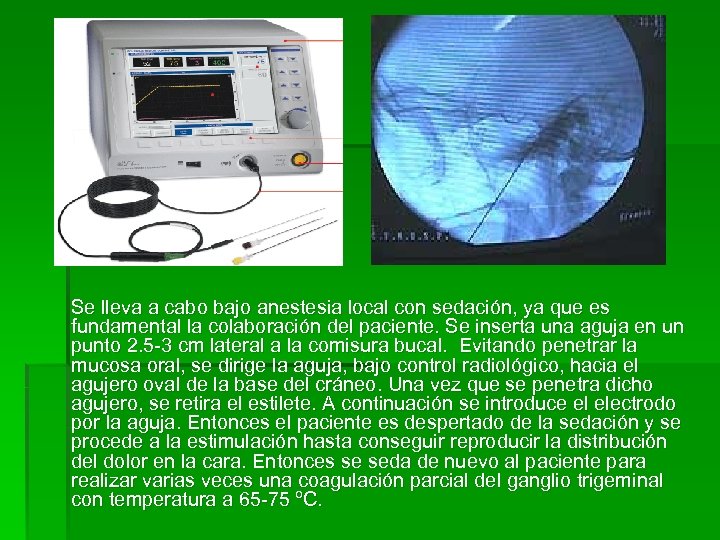

Se lleva a cabo bajo anestesia local con sedación, ya que es fundamental la colaboración del paciente. Se inserta una aguja en un punto 2. 5 -3 cm lateral a la comisura bucal. Evitando penetrar la mucosa oral, se dirige la aguja, bajo control radiológico, hacia el agujero oval de la base del cráneo. Una vez que se penetra dicho agujero, se retira el estilete. A continuación se introduce el electrodo por la aguja. Entonces el paciente es despertado de la sedación y se procede a la estimulación hasta conseguir reproducir la distribución del dolor en la cara. Entonces se seda de nuevo al paciente para realizar varias veces una coagulación parcial del ganglio trigeminal con temperatura a 65 -75 ºC.

Se lleva a cabo bajo anestesia local con sedación, ya que es fundamental la colaboración del paciente. Se inserta una aguja en un punto 2. 5 -3 cm lateral a la comisura bucal. Evitando penetrar la mucosa oral, se dirige la aguja, bajo control radiológico, hacia el agujero oval de la base del cráneo. Una vez que se penetra dicho agujero, se retira el estilete. A continuación se introduce el electrodo por la aguja. Entonces el paciente es despertado de la sedación y se procede a la estimulación hasta conseguir reproducir la distribución del dolor en la cara. Entonces se seda de nuevo al paciente para realizar varias veces una coagulación parcial del ganglio trigeminal con temperatura a 65 -75 ºC.